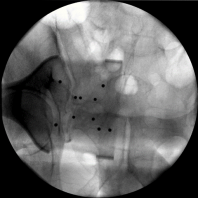

方案定制,手术医生根据患者影像资料在“大脑”的屏幕上设计并规划好手术方案。

STEP04

手术定位,在机器人眼睛的实时监测下,根据手术医生在机器人大脑制定的方案并准确传递给机器人手臂,引领医生精准定位。

STEP05

手术操作,医生根据机器人手臂的定位,结合患者的手术部位进行微创手术。